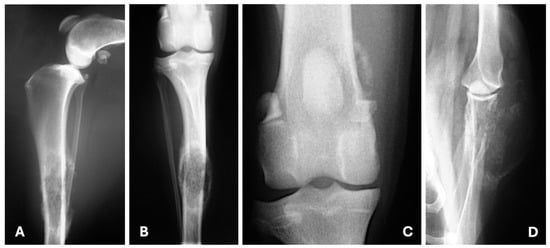

4.1. Radiography

- Lekshmi, S.L.; Nair, S.S.; Sajitha, I.S.; Ramankutty, S.; Narayanan, M.K.; John Martin, K.D. Radiographic Assessment of Pulmonary Metastatic Lesions in Superficial Cutaneous and Mammary Neoplasms in Dogs. J. Vet. Anim. Sci. 2021, 52, 393–398. [Google Scholar] [CrossRef]